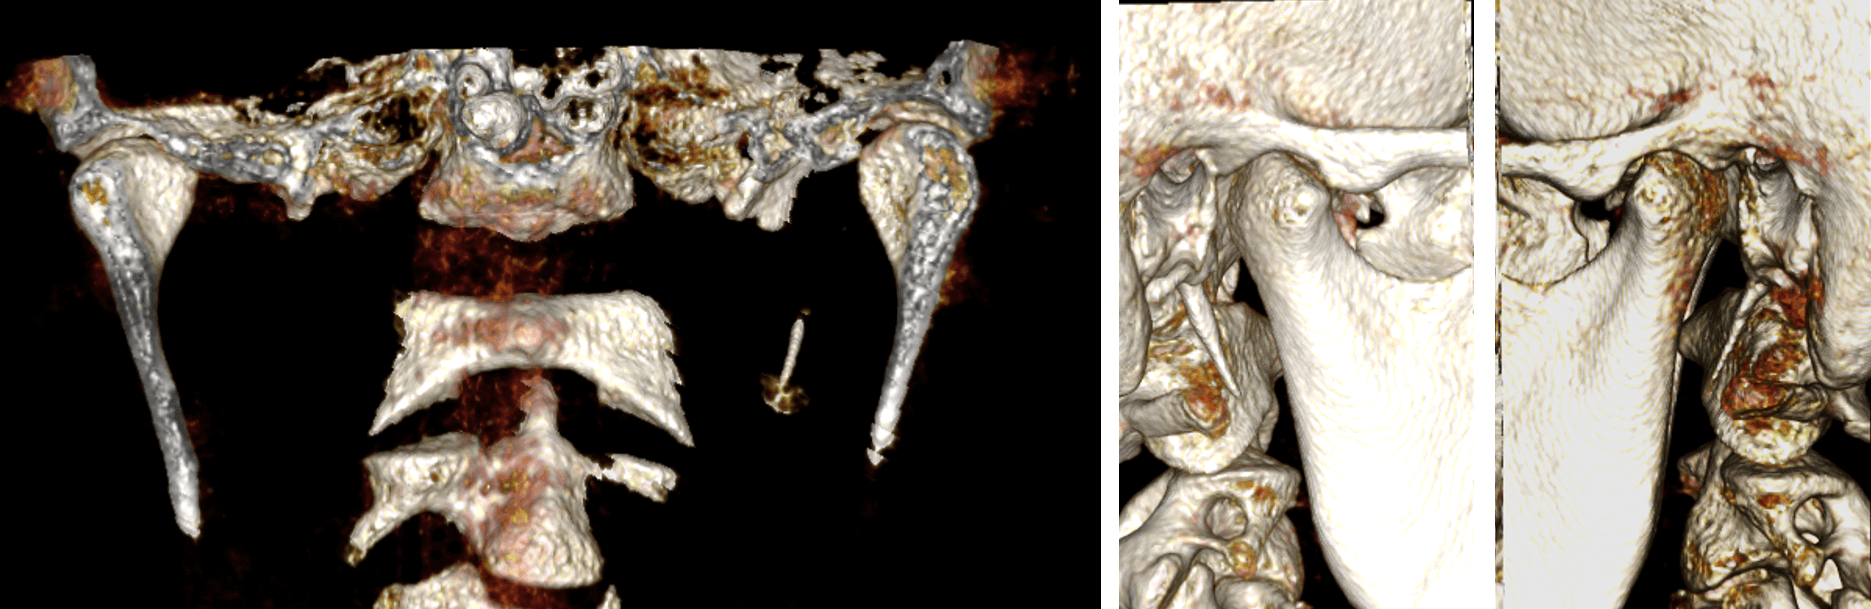

Fig.2

En las imágenes comparativas de ambos lados de la ATM (Fig.2) se observa la disminución del espacio articular en el corte coronal (superior) en el lado izquierdo y a nivel del polo lateral (flecha roja). Así mismo, se observa en el corte sagital (inferior) en el mismo un aparente cambio la morfología del cóndilo mandibular.